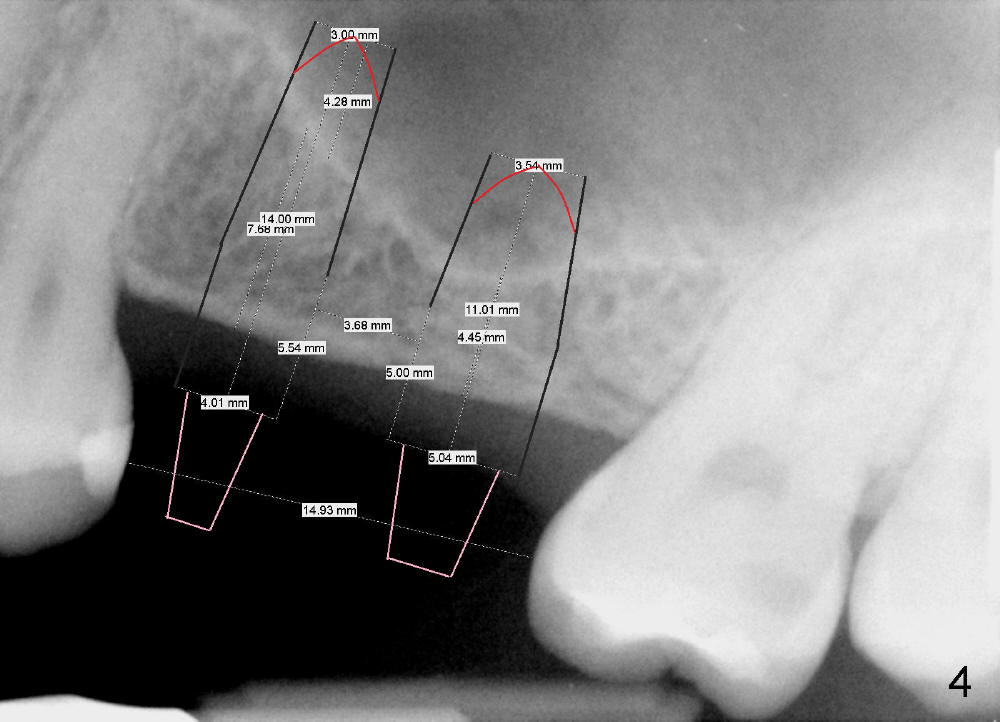

A 28-year-old lady (1,2) requests 3 more implants' restoration (Fig.1).  After wax up, the upper left quadrant (model) is duplicated and a surgical stent is fabricated (Fig.2).

Bone height is limited for implant placement at the sites of the 2nd premolar and the 1st molar (Fig.3: #13,14), 7.68 and 4.45 mm, respectively (Fig.4).  The depth of the pilot drills is controlled between 6 and 8 mm for #13 and less than 6 mm for #14 at the crest.

A 4x14 and 5x11 mm one-piece implants will be used (Fig.4; apices being pointed (red lines); while abutments being attached (pink lines)).  Approximately 4-5 mm implants will stick into the sinus space (but underneath the sinus membrane).  Immediate provisionals are to be splinted without any occlusal contact.